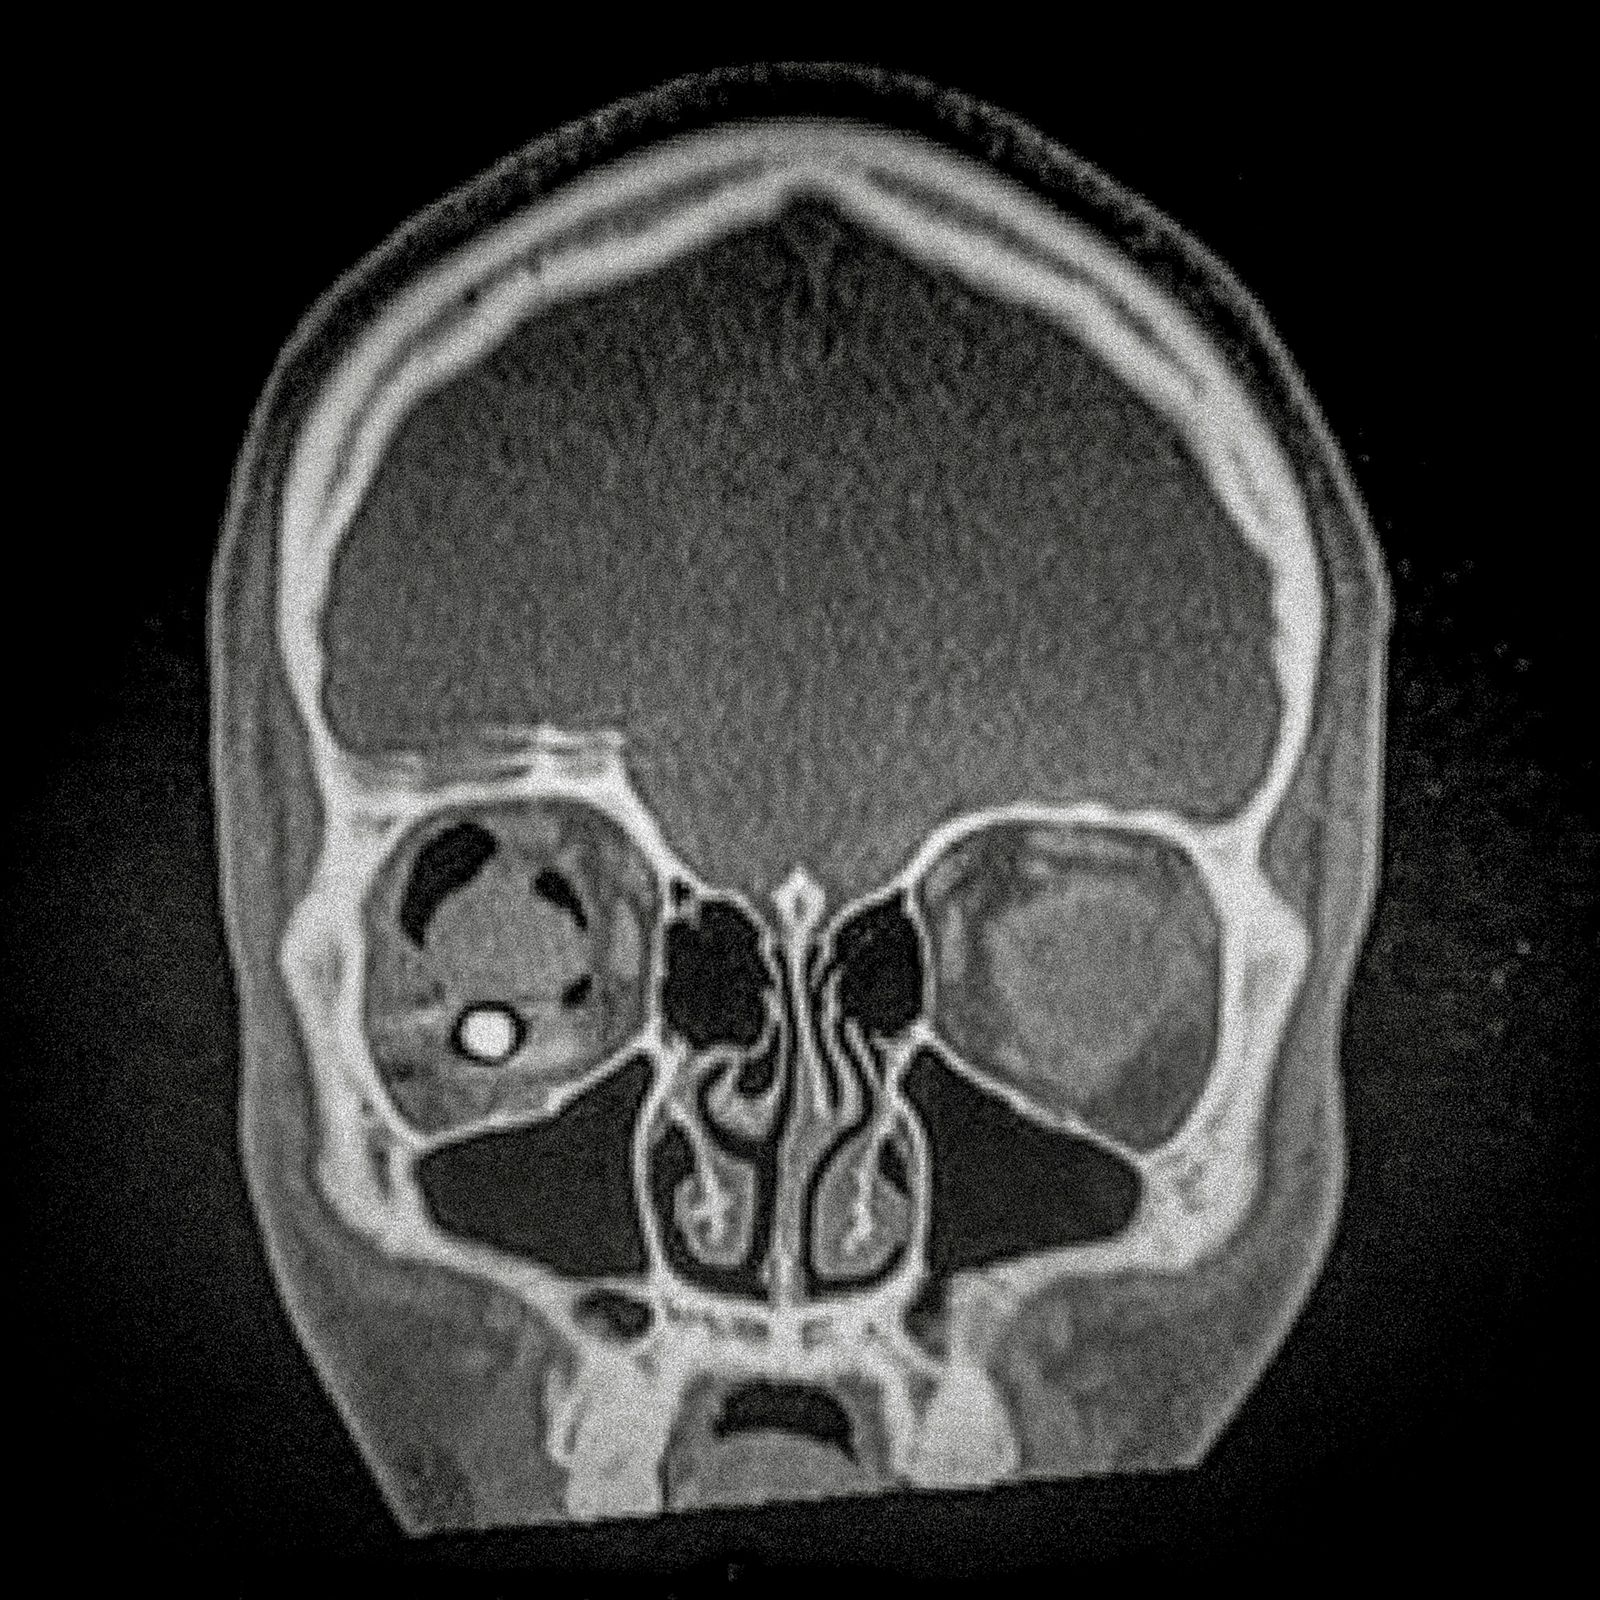

X-ray of Fabiola Campillai's face after she received a direct hit from a tear gas bomb fired by the carabineros chilean police, that caused her to lose both eyes.